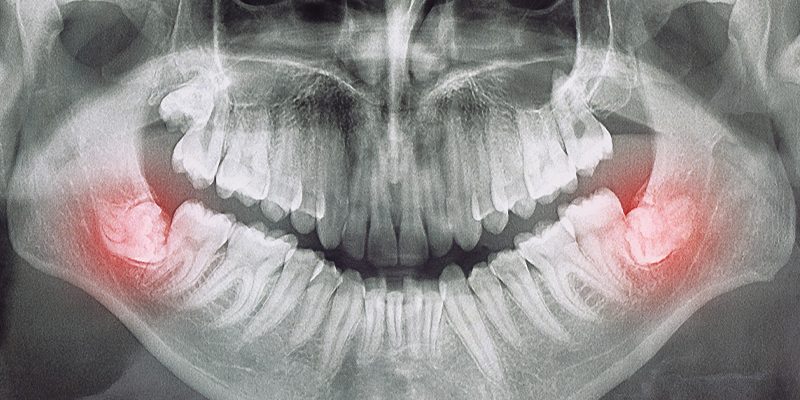

Die meisten chirurgischen Eingriffe können wir in unserer Praxis sicher und professionell durchführen. Für spezielle Eingriffe stehen Ihnen unser erfahrener Kieferchirurg und unsere kompetente Oralchirurgin zur Verfügung.